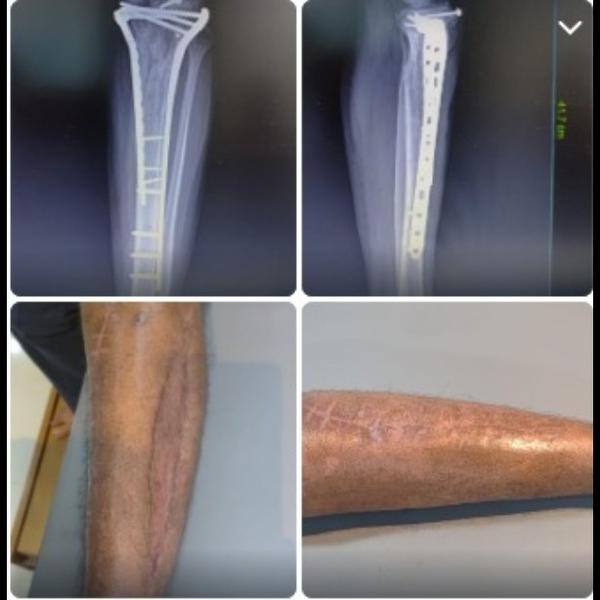

Type VI schatzker tibial condyle fracture !

Type 6 Schatzker Tibial Condyle fracture 4 months post op .Patient walking full weight bearing.